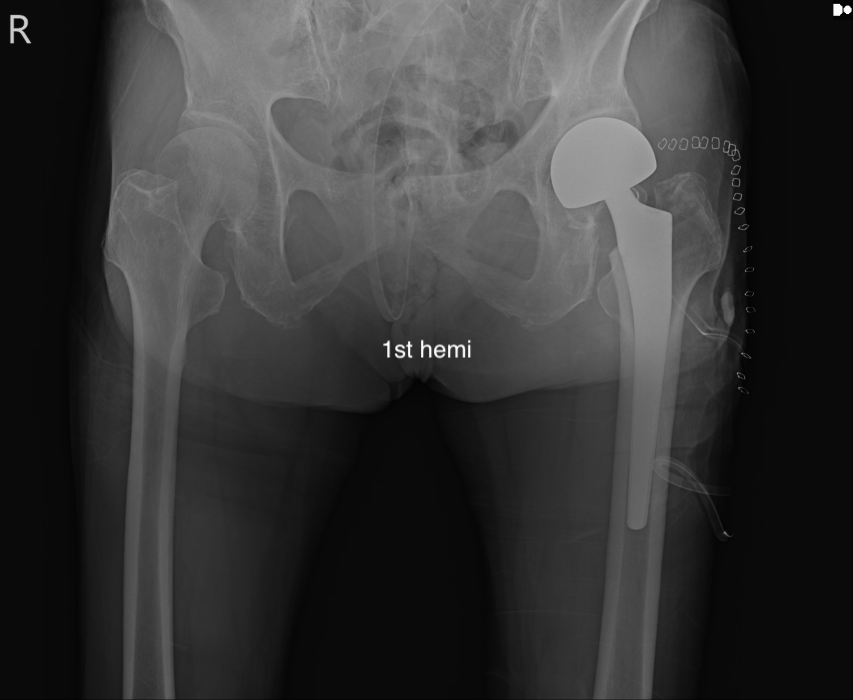

대퇴관절에서 대퇴골 경부가 골절이 있는 경우 시행하는 치료는

Osteosynthesis, 혹은 BPA, 혹은 THA 로 나뉠 수 있습니다. 최근 THA는 Dual Mobility Articulation 등을 사용해서 ROM 을 증가시키고 Dislocation 을 감소시키고 있긴 합니다.

THA 는 비구면 까지 고정을 하기 때문에 거의 마지막 수술이자 완벽한 수술이라고 볼 수 있습니다. 하지만 비골두가 안정적인 경우에는 골두치환만 해도 충분히 '인공관절' 기능을 할 수 있으며 수술적 시간이 매우 적습니다. 물론, 비골두가 implant 에 맞는 알맞은 구형 형태와 크기를 갖고 있어야 합니다. (36mm 를 많이 사용합니다. )

BPA 는 대퇴골두를 제거하고 인공 대퇴골두를 넣게 되는데, 인공 대퇴 골두와 이것을 감싸는 라이너가 있어 이 두개 사이의 움직임이 존재하며, 라이너와 골반 사이의 움직임이 존재하여 양극성(Bipolar) 인공관절 반치환술 이라고 불립니다.